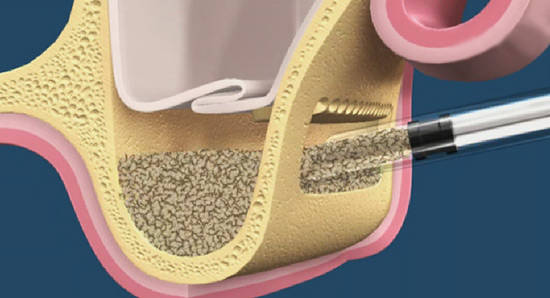

- Способ проведения операции — аутотрансплантация костного блока из ретромолярной области и ветви нижней челюсти с последующей фиксацией винтами. Это наиболее предсказуемый метод вертикальной остеопластики, дающий максимум положительных результатов. Ни один метод с использованием ксенотрансплантатов (Bioss, Cerabone, Easygraft и т. д.) такой статистики не дает.

- Под блоком, вероятно, будет небольшое пустое пространство вследствие неплотного соответствия поверхностей. Его заполняем аутокостной стружкой, взятой из того же участка, что и блок. В этом случае использование барьерной мембраны (BioGide, Jacon и т. д.) ОБЯЗАТЕЛЬНО.

- Забор костного блока целесообразнее сделать через ту же рану, что и основную операцию. Хотя с подбородка или бугра верхней челюсти донорский блок брать удобнее, мы думаем. в первую очередь, о комфорте пациентки — за одной раной, пусть и большой, ухаживать легче, чем за двумя.

- Качество швов и слизистой оболочки. Расхождение швов серьезно увеличивает риски потери блока, процентов на 20-25. А при использовании ксеногенных материалов — на 100%.

3. Остеопластика

И вот теперь, когда все нюансы обговорены, когда всё тщательно спланировано и рассчитано, мы приступаем к остеопластической операции.

Операция проводится под местной анестезией, совершенно безболезненна, и занимает, в среднем, от 60 до 90 минут.